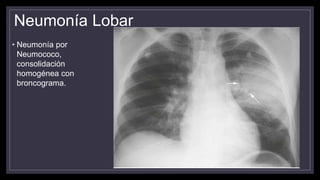

Neumonía Lobar

• Neumonía por

Neumococo,

consolidación

homogénea con

broncograma.